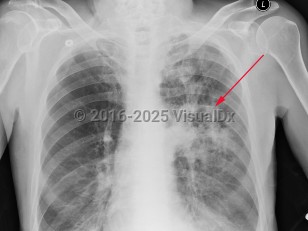

Imaging Studies image of Pulmonary nocardiosis - imageId=2955336. Click to open in gallery.  caption: 'Frontal chest x-ray with ill-defined cavitary opacity in the left upper lobe.'

Frontal chest x-ray with ill-defined cavitary opacity in the left upper lobe.